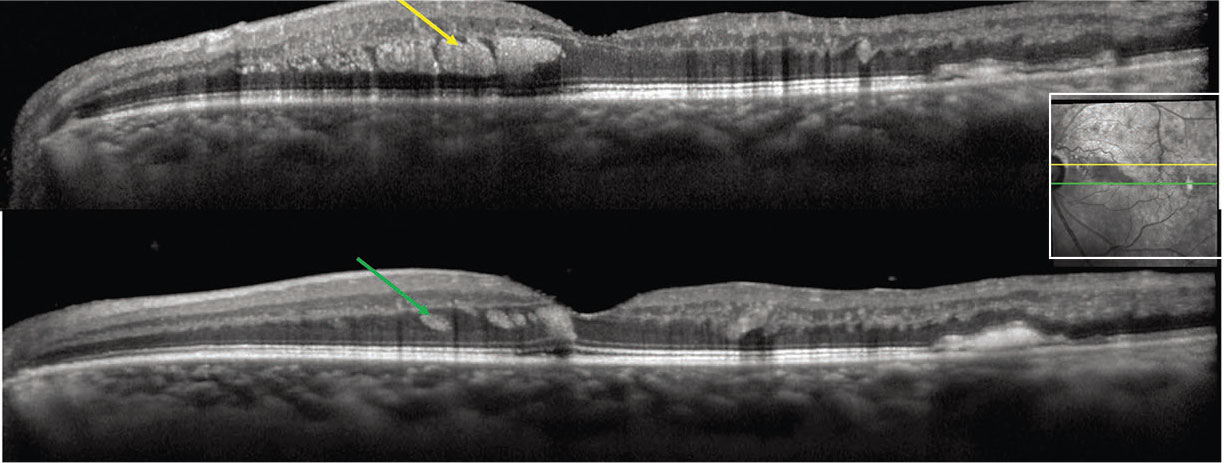

OCT findings of blood located within Henle fiber layer (HFL), referred to as Henle fiber layer hemorrhage or HH, have been described as characteristic hyperreflectivity from the hemorrhage delineated by the obliquely oriented fibers in the Henle layer (Figure 4).18 Clinical findings demonstrate deep hemorrhages that may exhibit a feathery margin and petaloid pattern radiating from the fovea or have a rounder appearance when located peripheral to the macula.

Figure 4. In Henle nerve fiber layer hemorrhage in a branch retinal vein occlusion, spectral-domain optical coherence tomography of the left eye shows oblique hyperreflectivity (yellow/green arrows) separated by hyporeflective striations corresponding to deep retinal hemorrhages in Henle fiber layer. The inset shows the near-infrared image. (Courtesy David Sarraf, MD) |